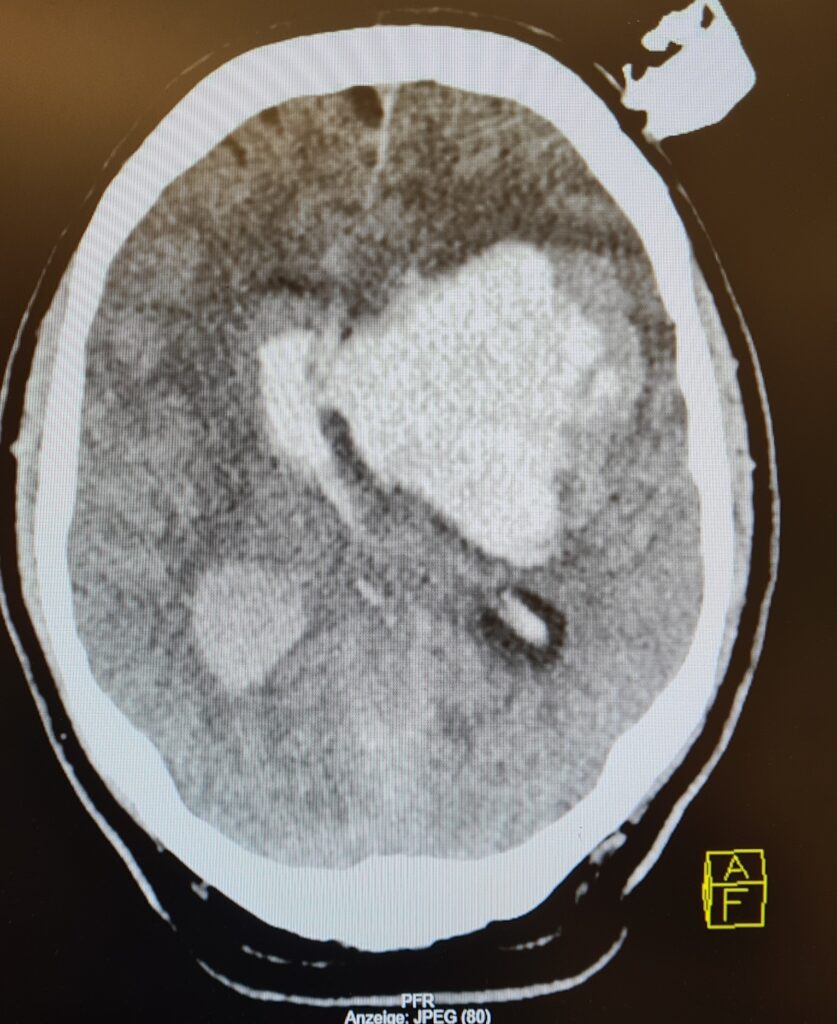

Sollte ein CT erfolgt sein (z.B. Schockraum bei schweren SHT, siehe hier), so können ICP-Anstiege wie folgt darstellbar sein: Herniation, Ventrikelkompression, Mittellinienshift, Verstreichen der Sulci, Verlust der Grau-Weiß-Differenzierung (indirekter Hinweis auf Hirnödem). Hier könnt ihr ein paar Originalbilder aus meiner Tätigkeit begutachten. Beachtet die Kompressions- und Raumforderungsphänomene.